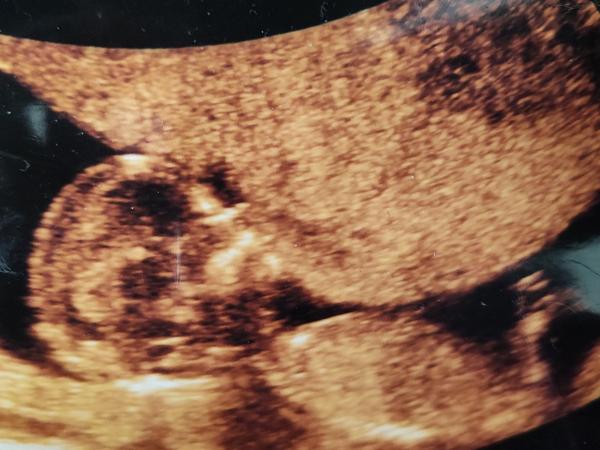

Ahoj holky, jen z mé zvědavosti a především netrpělivosti bych se chtěla zeptat i nestranných osob co vidí na ultrazvuku za pohlaví. Respektivě, co si dokážete odhadnout na základě pohlavního hrbolku. 🙈😅 Je to fotka z prvního screeningu, kde nás pan doktor řekl, že těžko říci, je to má tak půl na půl.

Holka. Je to krásně vidět, hrbolek téměř vodorovně s páteří. Dejte vědět výsledek 😉🍀

@sebinka123 děkuji za odpověď, a který hrbolek myslíte, že to je, myslím, že jej z části zakrývá ta nožička

@sebinka123 To rozhodně není pohlavní hrbolek. 😊

@sebinka123 kloub nožičky?